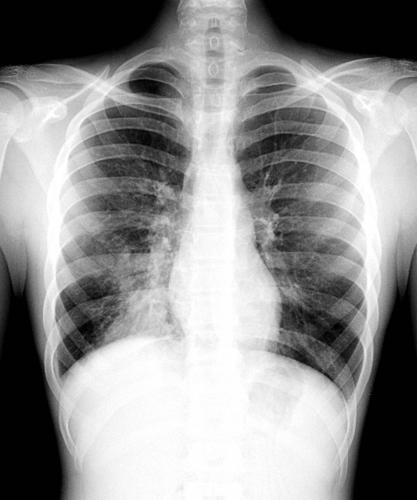

Самым результативным способом выявления болезни легких, является прослушивание новорожденного на присутствие хрипов в области грудной клетки и рентгеновское исследование.

Диагностика пневмонии у новорожденных проводиться с помощью рентгенологических и лабораторных исследований. Кроме того, верная постановка диагноза невозможна без учета клинических симптомов и данных анамнеза. Если у крохи выявлено воспаление легких, нужна госпитализация.

- Сегментарная – данный вид воспаления развивается после ОРВИ или другой вирусной инфекции. Выявить его можно только с помощью рентгеновского снимка, так как симптоматика очень незаметная и поставить диагноз на ее основании невозможно. Выздоровление, как правило, наступает на третью неделю после начала лечения.